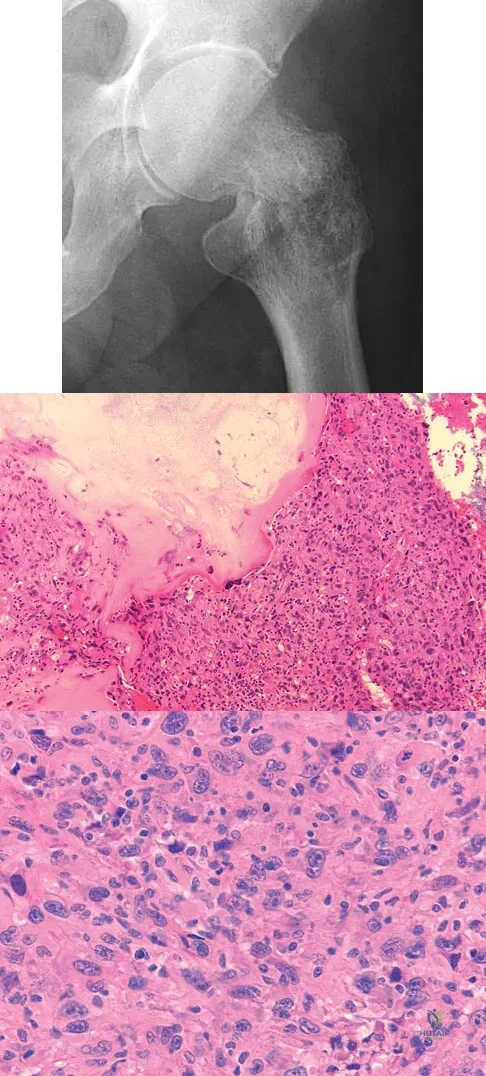

A 21-year-old man has had right groin pain for the past year. A radiograph, CT scan, MRI scans, and a biopsy specimen are shown in Figures 50a through 50e. What is the most likely diagnosis?

A 73-year-old man stepped off a street curb and felt a crack in his left hip. He is now unable to bear weight. A radiograph is shown in Figure 54a. Biopsy specimens are shown in Figures 54b and 54c. What is the most likely diagnosis?

A 9-year-old girl reports progressive right knee pain. Radiographs are shown in Figures 59a and 59b. Work-up reveals no other sites of disease. Low- and high-power photomicrographs are shown in Figures 59c and 59d. What is the most appropriate treatment?